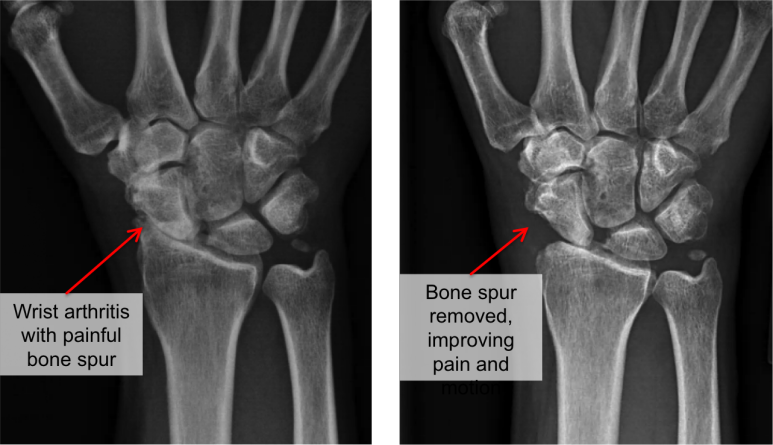

3) X-ray 검사

- 손목관절의 관절사이간격이 좁아진경우나 골극(Osteophytes), 경화(Subchondral bone sclerosis)을 확인할 수 있는 아주 중요한 검사입니다.

- 요골 - 주상골 관절

- 요골 - 월상골 관절

- 주상골 - 월상골 관절